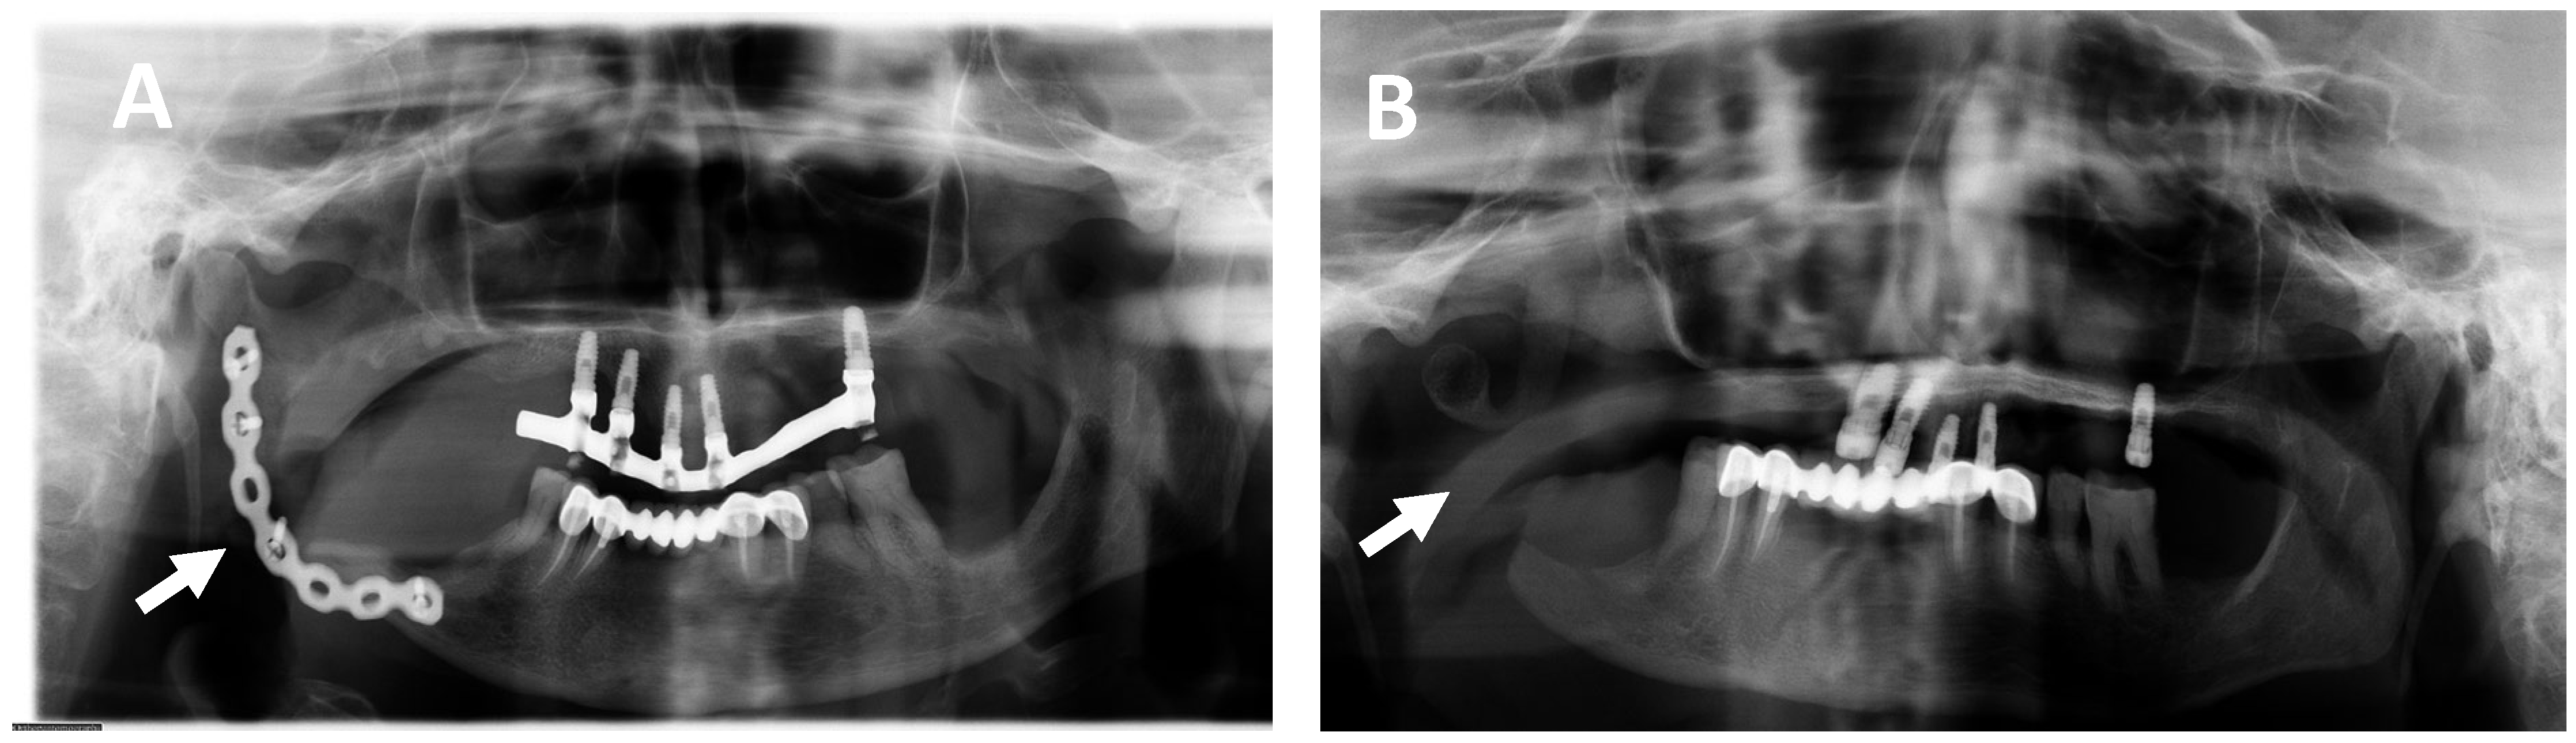

2.1. Clinical and Histological Manifestations of the Tumors